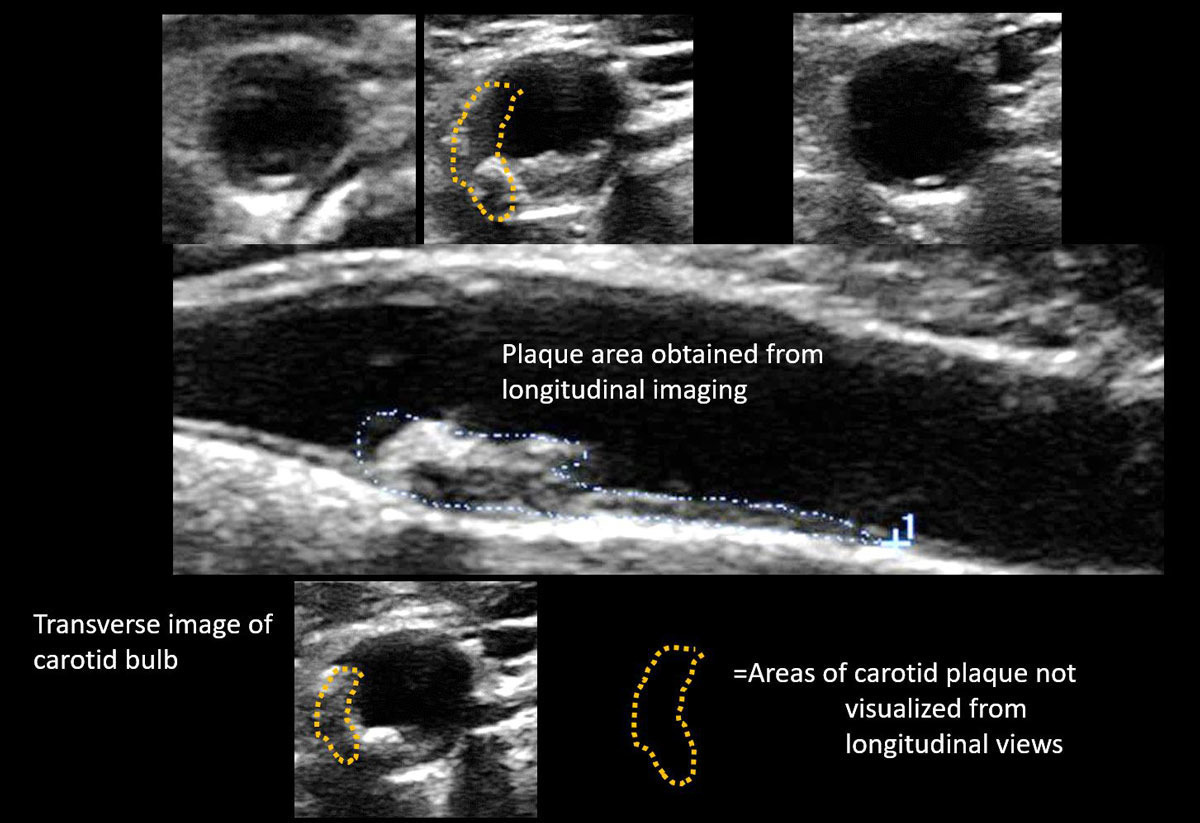

경동맥 플라크

플라크는 혈관 벽에 국소적으로 형성된 병변으로, 크기와 성상에 따라 위험도가 달라집니다. 단단하고 안정적인 플라크보다, 표면이 불규칙하거나 내부가 불균질한 불안정 플라크가 더 위험합니다. 경동맥 초음파는 이러한 플라크의 위치와 특성을 비교적 명확하게 확인할 수 있어, 향후 혈전 발생 가능성을 예측하는 데 도움을 줍니다.